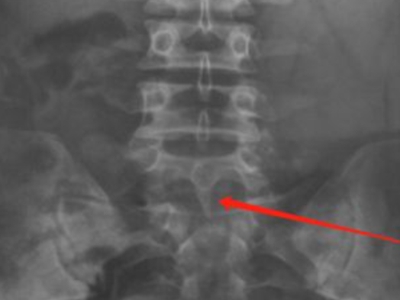

隐性脊柱裂腰部拍片两侧不对称有裂口图

对隐性脊柱裂患者的腰部进行影像检查,会见到椎板有一处畸形,椎弓板缺损,中间有裂口,与棘突一侧融合,另一侧不融合,患者无自觉症状,属一种先天发育畸形疾病。